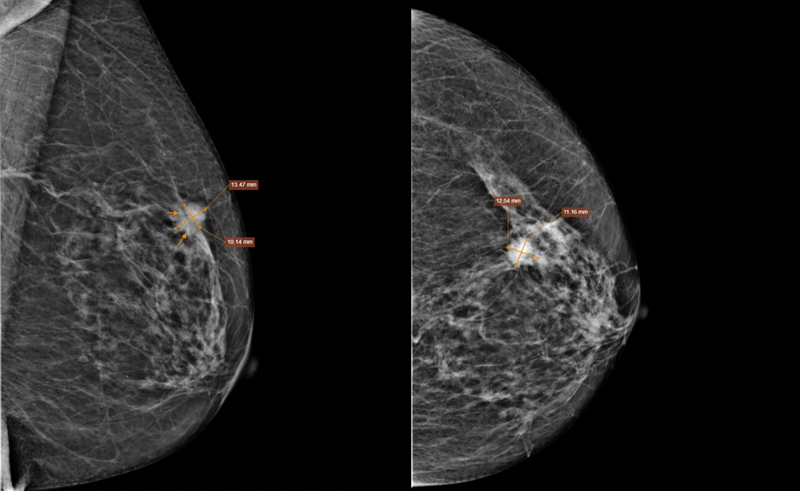

Chụp X-quang tuyến vú kỹ thuật số (Mammography) phát hiện nốt tăng đậm độ nhu mô vú trái, phân loại BIRADS 5.

Chụp X-quang tuyến vú ghi nhận nốt tăng đậm độ nhu mô vú trái, phân loại BIRADS 5. Ảnh Medlatec